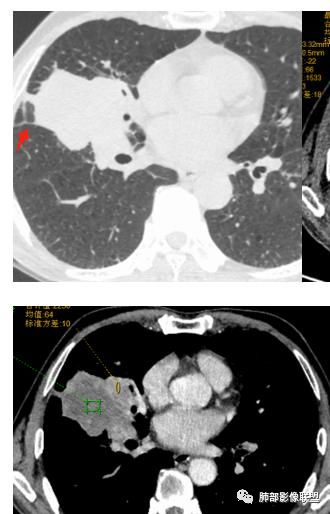

老年男性,体检发现。

右肺中叶肿块影,向上向下侵犯叶间裂,边缘膨隆,分叶,毛刺。肿块内部密度不均,大片坏死。血管走形尚可。中叶支气管狭窄截断。增强不均匀强化。纵隔淋巴结肿大,部分融合。

考虑恶性,腺癌>鳞癌。鉴别炎肌母。

我有一个疑问,这个病灶一开始到底起源于哪一个叶?

初学者:

可以看到斜裂一侧往上一侧往下,那么就是说病灶应该是起源中叶,往上,往下侵犯这样

尘缘:

@吴婧南京市第一医院 主体应该还是中叶

如是上叶的,叶间裂的方向应该是往一侧压得

只有这个位置起源得才能做到,将叶间裂上下往不同方向推

斜裂向下推移了,水平裂向上推移了。

@吴婧南京市第一医院 这个从影像表现,坏死情况,以及叶裂推移情况与支气管推移情况来看,还是支持中叶间质来源,外朝内生长,同时向上,向下,向内都有推移作用。

下半段斜裂推移朝下

水平裂推移朝上

定在中叶应该没问题

是的,中叶基本肯定。

嗯,主体在中叶

上叶应该是侵犯,下叶应该是叶裂漏出来的。